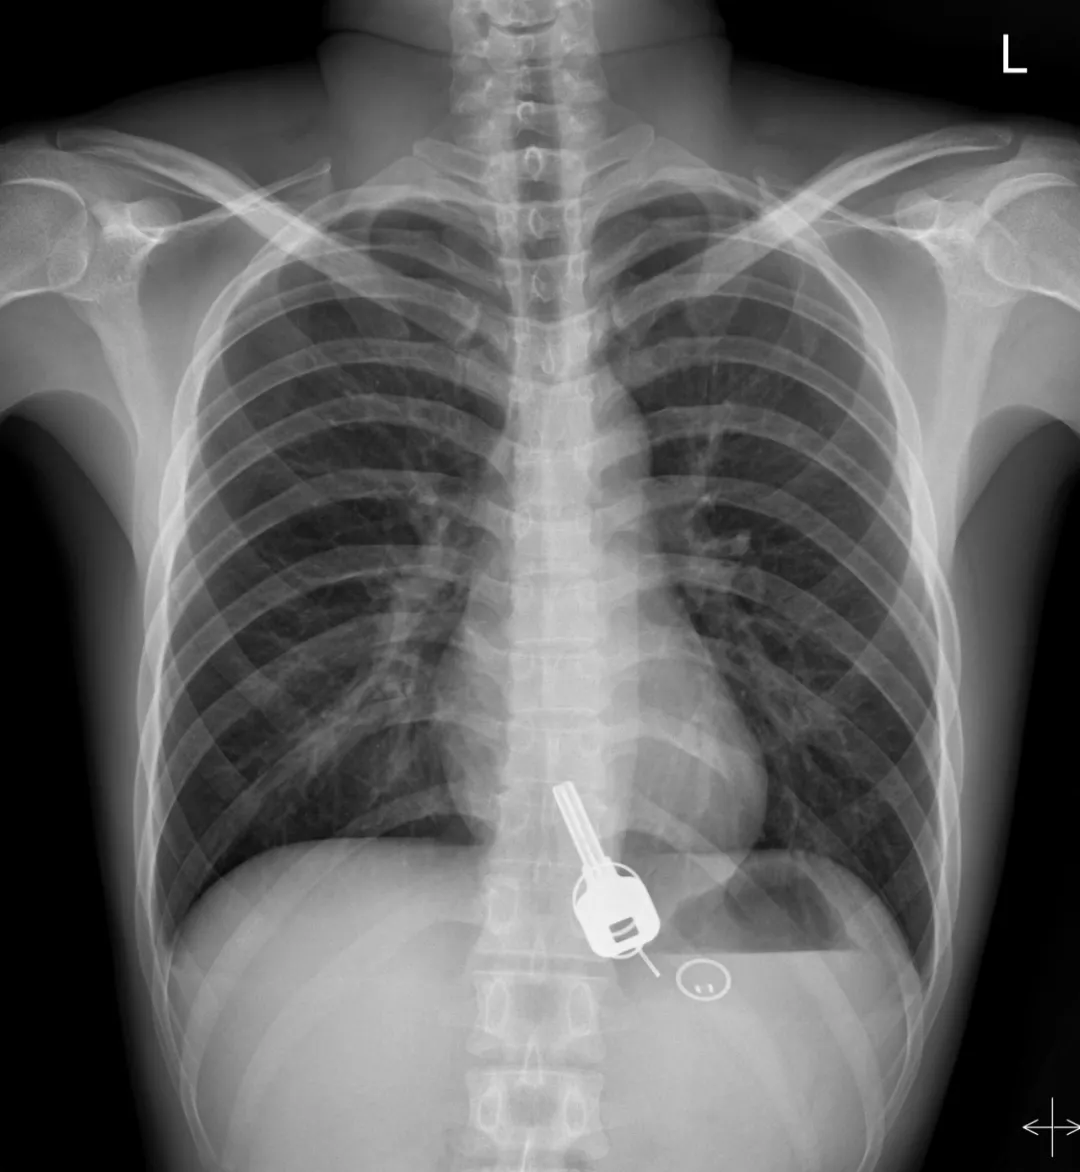

廣東東莞的常先生酒后回家找不到鑰匙,酒醒后他感到胸口疼痛,去醫(yī)院一查,發(fā)現(xiàn)一把鐵鑰匙、2個(gè)鑰匙扣、1個(gè)門禁牌清楚顯示在肚子胃區(qū)的位置上。

醫(yī)生準(zhǔn)備在胃鏡下取出鑰匙,不料,因鑰匙太大在常先生喉嚨附近食管入口處卡住了,取不出來(lái),最后,醫(yī)生決定給常先生做無(wú)痛胃鏡,麻醉后,常先生食管入口處肌肉松弛,鑰匙終于順利取出!。